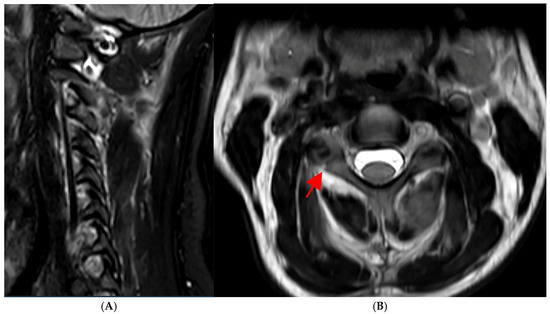

2.1. Preoperative Planning